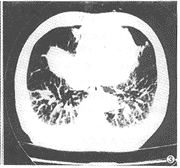

4例肝硬化患者末梢肺血管显著扩张,呈杵状(图2),扩张的血管与胸膜相连。另有3例呈蜂窝状血管扩张(图3)。上述改变均位于肺基底部,5例为双侧,2例为单侧。非肝硬化组肺部无明显改变。

图3 肝硬化失代偿期,CT扫描显示肺血管呈“蜂窝”状扩张

, 百拇医药 肝硬化所致肺部改变的CT表现未见大宗病例报道。本研究中CT表现主要为肺血管末梢明显杵状扩张或海绵状扩张,多位于基底部。这种改变的原因虽不明确,但可解释患者的直立性缺氧。当患者由卧位变为坐位或立位时,肺内血流重新分布,使更多的血液流向肺基底部扩张的血管,以致通气-血流比例失调,PaO2降低。肺血管杵状改变的病例其低氧血症也比较明显。